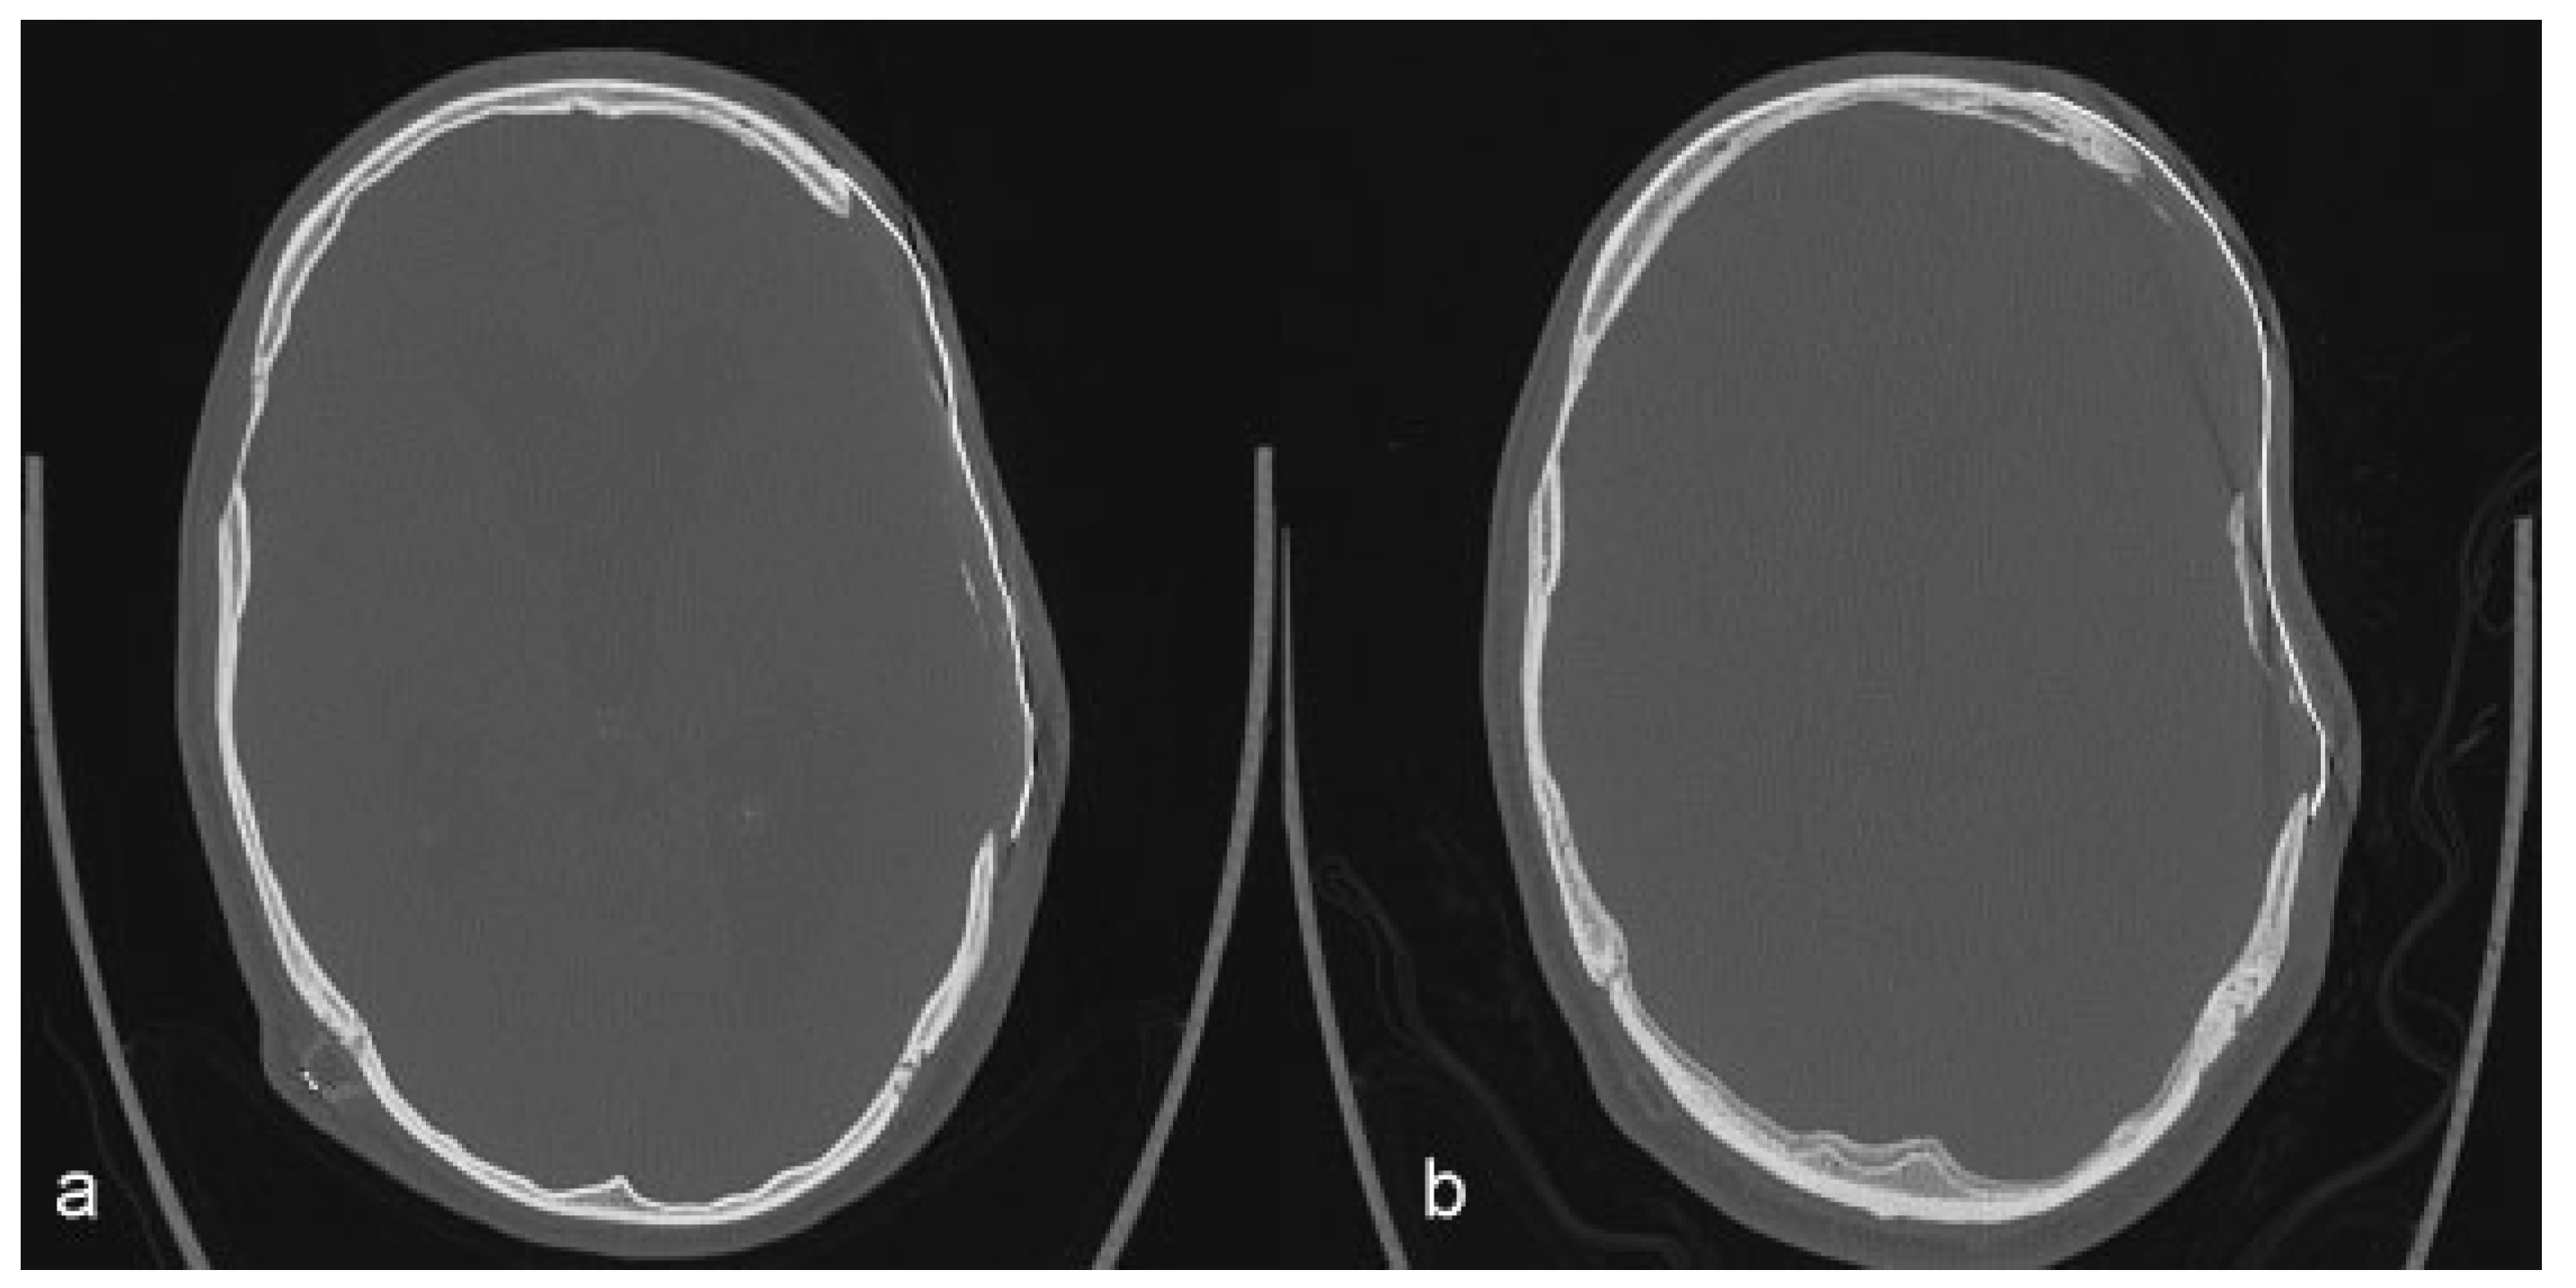

De Water, V.R.; dos Santos Rubio, E.J.; Schouten, J.W.; Koudstaal, M.J. Deformation of a Titanium Calvarial Implant following Trauma: A Case Report. Craniomaxillofac. Trauma Reconstr. 2016, 9, 158-161. https://doi.org/10.1055/s-0035-1567810